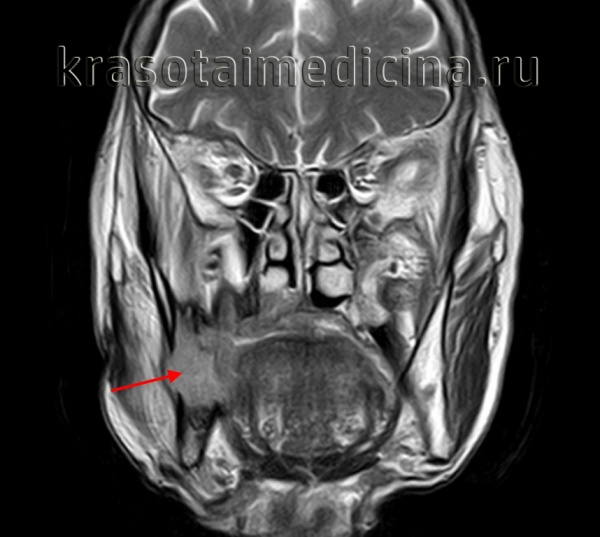

- МРТ (магнитно-резонансная томография) — покажет патологию в мягких тканях.

Хотя амелобластома крайне редко становится злокачественной (описано около 30 случаев метастазирующей амелобластомы [1] ), целесообразно провести комплексное обследование: МРТ всего организма и анализ крови на онкомаркеры (Ki-67, SOX2). Эти исследования помогут заподозрить наличие злокачественной амелобластомы. Достоверно определить злокачественность опухоль можно только гистологическим методом после операции.